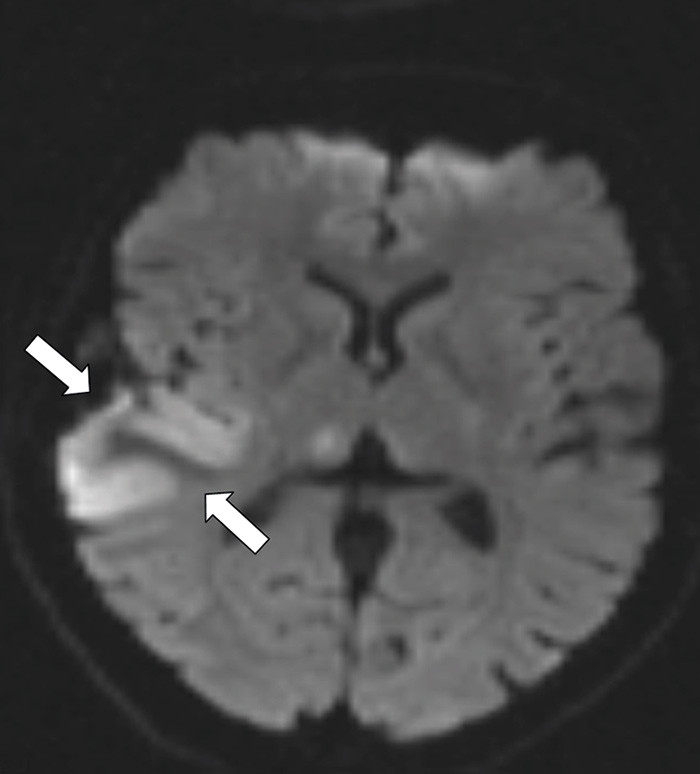

En tidligere frisk kvinne i 40-årsalderen hadde fra dagen før innleggelsen morgenhodepine og oppkast. Hun var ikke-røyker og brukte ingen medisiner eller hormoner. Innleggelsesdagen utviklet hun akutt parese i venstre ansiktshalvdel, venstresidig armparese og dysartri. Hun hadde forbigående rykninger i venstre ansiktshalvdel. Cerebral CT utført ved lokalsykehuset viste en høyattenuerende lesjon i høyre temporoparietallapp (bilde kun på nett). D-dimer var 0,8 mg/l (normalt < 0,4). Man mistenkte vaskulær hendelse i høyre hemisfære. Cerebral MR-venografi ved universitetssykehuset dagen etter viste en intraluminal venøs fyllingsdefekt svarende til høyre vena Trolard (bildet til venstre). Diffusjonsvektet cerebral MR viste en blanding av vasogent og cytotoksisk ødem temporoparietalt, typisk for venøst infarkt (bildet til høyre). Testing av forstyrrelser i trombose-koagulasjonssystemet viste aktivert protein C-resistens 0,66 (normalt 0,85 – 1,15). Pasienten fikk antikoagulasjonsbehandling og seks dager etter initiering av antikoagulasjon var ny cerebral MR-venografi normalisert. Hun ble utskrevet uten sekvele.

Cerebral venetrombose gir ofte hodepine, og kan gi nevrologiske utfall og epileptiske anfall ved samtidig infarktutvikling. Aktivert protein C-resistens disponerer for cerebral venetrombose, som er en sjelden (0,5 – 1 %) årsak til hjerneslag (1). Rask diagnostikk og behandling er vesentlig for prognosen. CT- og MR-venografi kan med høy sensitivitet og spesifisitet ikke-invasivt visualisere venøse cerebrale tromber.